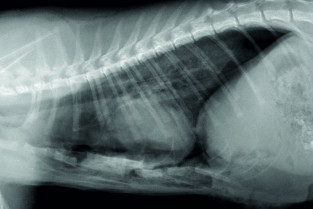

Le GEIM vous propose une séance de travaux pratiques de radiographies sur le thorax. Tous les aspects sont abordés sous la forme de TP de lecture de radiographies numériques sur station de travail Osirix sur Mac (3 vétérinaires maximum/ordinateur).

- adopter une méthodologie pour interpréter les affections de la cage thoracique, de la plèvre, et du médiastin chez les carnivores domestiques ;

- décrire l’aspect normal et anormal de la cage thoracique, de la plèvre, et du médiastin chez les carnivores domestiques.